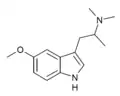

α-Alkyltryptamines are a group of substituted tryptamines which possess an alkyl group, such as a methyl or ethyl group, attached at the alpha carbon, and in most cases no substitution on the amine nitrogen.[17][18][19] α-Alkylation of tryptamine makes it much more metabolically stable and resistant to degradation by monoamine oxidase, resulting in increased potency and greatly lengthened half-life.[19] This is analogous to α-methylation of phenethylamine into amphetamine.[19]

N,N-Dimethyl-5-MeO-αMT (5-MeO-α,N,N-TMT) | (2-(5-methoxy-1H-Indol-3-yl)-1-methyl-ethyl)dimethylamine | 101831-90-7 |